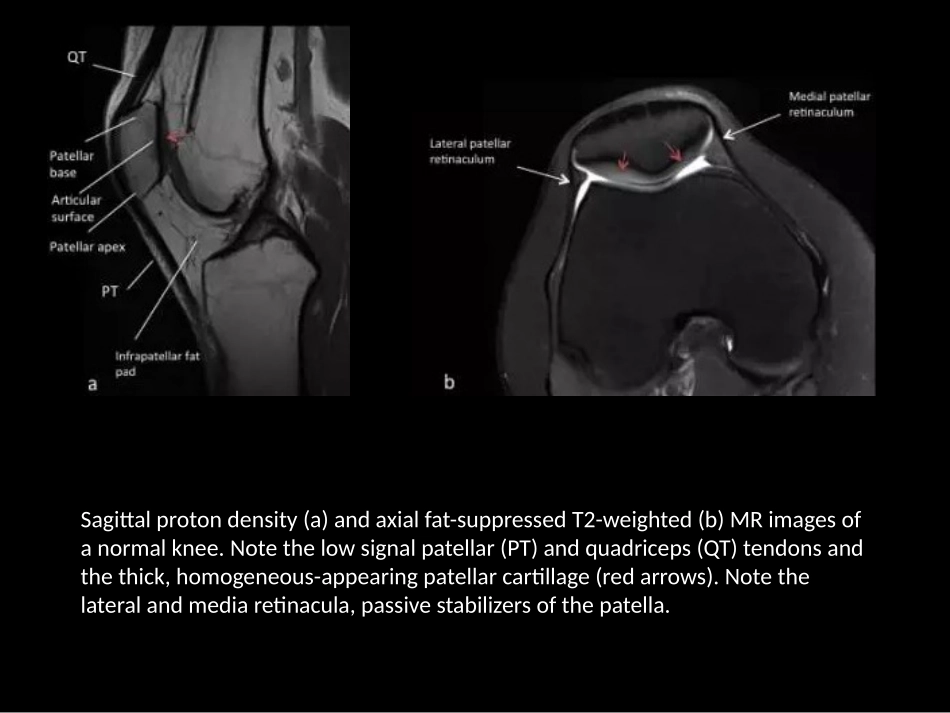

Normalradiographsofthekneewithanteroposterior(a),lateral(b),andaxial(c)biewdemonstratenormalpatellarpositionandmorphology.Theanteroposteriorprojection(a)isusefulforevalutingthefemurandproximaltibia,femoralandtibialplateaus.Thelateralprojectionisusefulforevaluatingpatellarheight,patellofemoralcompartment,suprapatellarrecess(SR),quadricepstendon(QT),patellartendon(PT).Theaxialviewofthepatellahelpsinassessmentoftheshapeofthepatella,notemedia(MF)andlateral(LF)patellarfacetsandmedianridge(MR).Alsonotenormalandroughanteriorpatellarcortex(bluearrow).Sagittalprotondensity(a)andaxialfat-suppressedT2-weighted(b)MRimagesofanormalknee.Notethelowsignalpatellar(PT)andquadriceps(QT)tendonsandthethick,homogeneous-appearingpatellarcartillage(redarrows).Notethelateralandmediaretinacula,passivestabilizersofthepatella.In1941,Wibergclassifiedpatellarshapeintothreedifferentmorphologies:TypeI(a)demonstratesroughlysymmetricandequal-sized,concavemedial(MF)andlateral(LF)patellarfacets.TypeII(b)showsamedialfacetthatisslightlysmallerthanthelateralfacetandaconcavelateralfacet.TypeIII(c)alsoshowsasmallerandmoreverticallyorientedmedialpatellarfacet,whichisassociatedwithmaltrackingdisorders[18].5-year-oldmalewithhereditaryosteo-onychodysplasia(nail-patellasyndrome).AP(a),later(b),andaxial(c)viewsofthekneedemonstratecompleteabsenceofthebilateralpatellarossificationcenters.Anteroposteriorandaxialradiographs(a)showbilateral,well-corticatedossifiedfragmentsinthesuperolateralaspectofthepatellas(arrows).CoronalandaxialT2-weightedfat-suppressedMRimage(b)showthewell-corticatedossifiedfragment.Notethenormalbonemarrowsignalandcartilageacrossthesynchondrisis,Thewell-corticatednatureofthefragmentandlackofabnormalmarrowsignalhelptodifferentiatethisentityfromapatellarfracture.Anteroposterior,lateral,andaxialradiographs(s)showalucent,roundlesionwithwell-definedmarginsatthesuperolateralaspectofthepatella(arrows).SagittalprotondensityandaxialT2-weightedfat-suppressedMRimages(b)showafocalsubchondralosseousdefectwithintact-appearingoverlyingcartilage;thecartilageisthickened,andfillsthedefect.Thereisnormalbonemarrowsignalandsmooth,homogeneoussignalofthearticularcartilage.Congenitalpatellaaltaisananatomicriskfactorforpatellofemoralinstability.Theinsall-Salvatiindexistheratioofthelengthofthepatella(PL)tothepatellartendon(PT).Thenormalvalueisbetween1.0and1.2,withincreasedvaluesindicatingpatellaaltaanddecreasedvalueindicatingpatellabaja.Lateralradiograph(a)atapproximately30degreesofkneeflxionshowsanoemallyplacedpatella,withInsall-Salvatiindexof1.1.Lateralradiograph(b)ofan8-year-oldmaleshowspatellaalta,withInsall-Salvatiindexmeasuring1.8.AxialT2-weightedtubrospinechoMRimage(c)formthissamepatientshowsfindingofalateralpatellardislocation.Thereisbonemarrowedemaofthemedialaspectofthepatella(arrow)anddisruptionofthemedialpatellarretinaculum(asterisk).Thispatienthadahistoryofrecurrentdislocations,likelyduetohiscongenitalpatellaalta.Anteroposterior(a)andlateral(b)radiographsofa15-year-oldfemalepatientwithcingenitalright-sidedpatellabaja.Lateralradiographsofapatientoneyearfollowingtotalkneearthroplastydemonstratespatellabaja.Thepatellartendonisscarredtotheuppertibia(arrow).Patellabajamayalsobeseeninassociationwithneuromusculardiseases.Fromtal(c)andlateral(d)radiographsinthispatientwithahistoryofpolioshowmarkedpatellabaja.Alsonitethat...